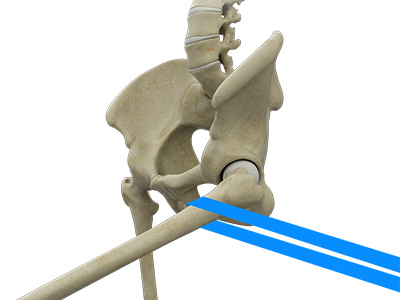

The hip joint is the junction where the hip joins the leg to the trunk of the body. It is comprised of two bones: the thigh bone or femur and the pelvis which is made up of three bones called ilium, ischium, and pubis. The ball of the hip joint is made by the femoral head while the socket is formed by the acetabulum. The Acetabulum is a deep, circular socket formed on the outer edge of the pelvis by the union of three bones: ilium, ischium, and pubis. The lower part of the ilium is attached by the pubis while the ischium is considerably behind the pubis. The stability of the hip is provided by the joint capsule or acetabulum and the muscles and ligaments which surround and support the hip joint.

The head of the femur rotates and glides within the acetabulum. A fibrocartilagenous lining called the labrum is attached to the acetabulum and further increases the depth of the socket.

The femur or thigh bone is one of the longest bones in the human body. The upper part of the thigh bone consists of the femoral head, femoral neck, and greater and lesser trochanters. The head of the femur joins the pelvis (acetabulum) to form the hip joint. Next, to the femoral neck, there are two protrusions known as greater and lesser trochanters which serve as sites of muscle attachment.